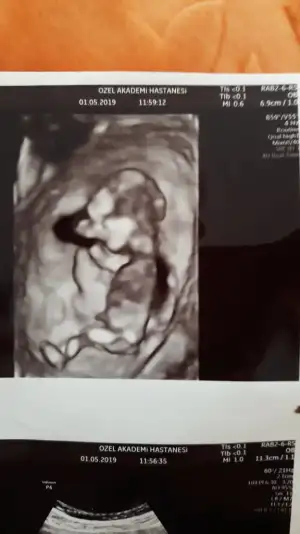

Kontrolden çıktık sata gore 12+4 ultrasona gore geriden gelen bebişim bugun 13+2 cikti :) boyu 6.5 cm olmuş ense ve burun kemiğine iyi dedi kac diye sorunca 1den kucuk merak etme sorun yok dedi doktorum;) kan verdim 1 hafta sonra çıkacakmış sonuç doktorum cinsiyetle ilgili de kıza benziyor ama kesin değil dedi ve ben basından beri kiz hissediyorum:) en son gittiğimde mercimek tanesi kadardı ama bugun gercekten bir bebek gordum zıplayan kayan ellerini oynatan, Rabbimin gerçekten bir mucizesi Allahım hepimize boyle guzel haberler almayi nasip etsin inşallah tekrar :) 15567063923235918574424562188093.webp 15567064171896032461299685616764.webp

Kontrolden çıktık sata gore 12+4 ultrasona gore geriden gelen bebişim bugun 13+2 cikti :) boyu 6.5 cm olmuş ense ve burun kemiğine iyi dedi kac diye sorunca 1den kucuk merak etme sorun yok dedi doktorum:KK66: kan verdim 1 hafta sonra çıkacakmış sonuç doktorum cinsiyetle ilgili de kıza benziyor ama kesin değil dedi ve ben basından beri kiz hissediyorum:) en son gittiğimde mercimek tanesi kadardı ama bugun gercekten bir bebek gordum zıplayan kayan ellerini oynatan, Rabbimin gerçekten bir mucizesi Allahım hepimize boyle guzel haberler almayi nasip etsin inşallah tekrar :)Eki Görüntüle 2264270 Eki Görüntüle 2264272 Eki Görüntüle 2264270 Eki Görüntüle 2264272